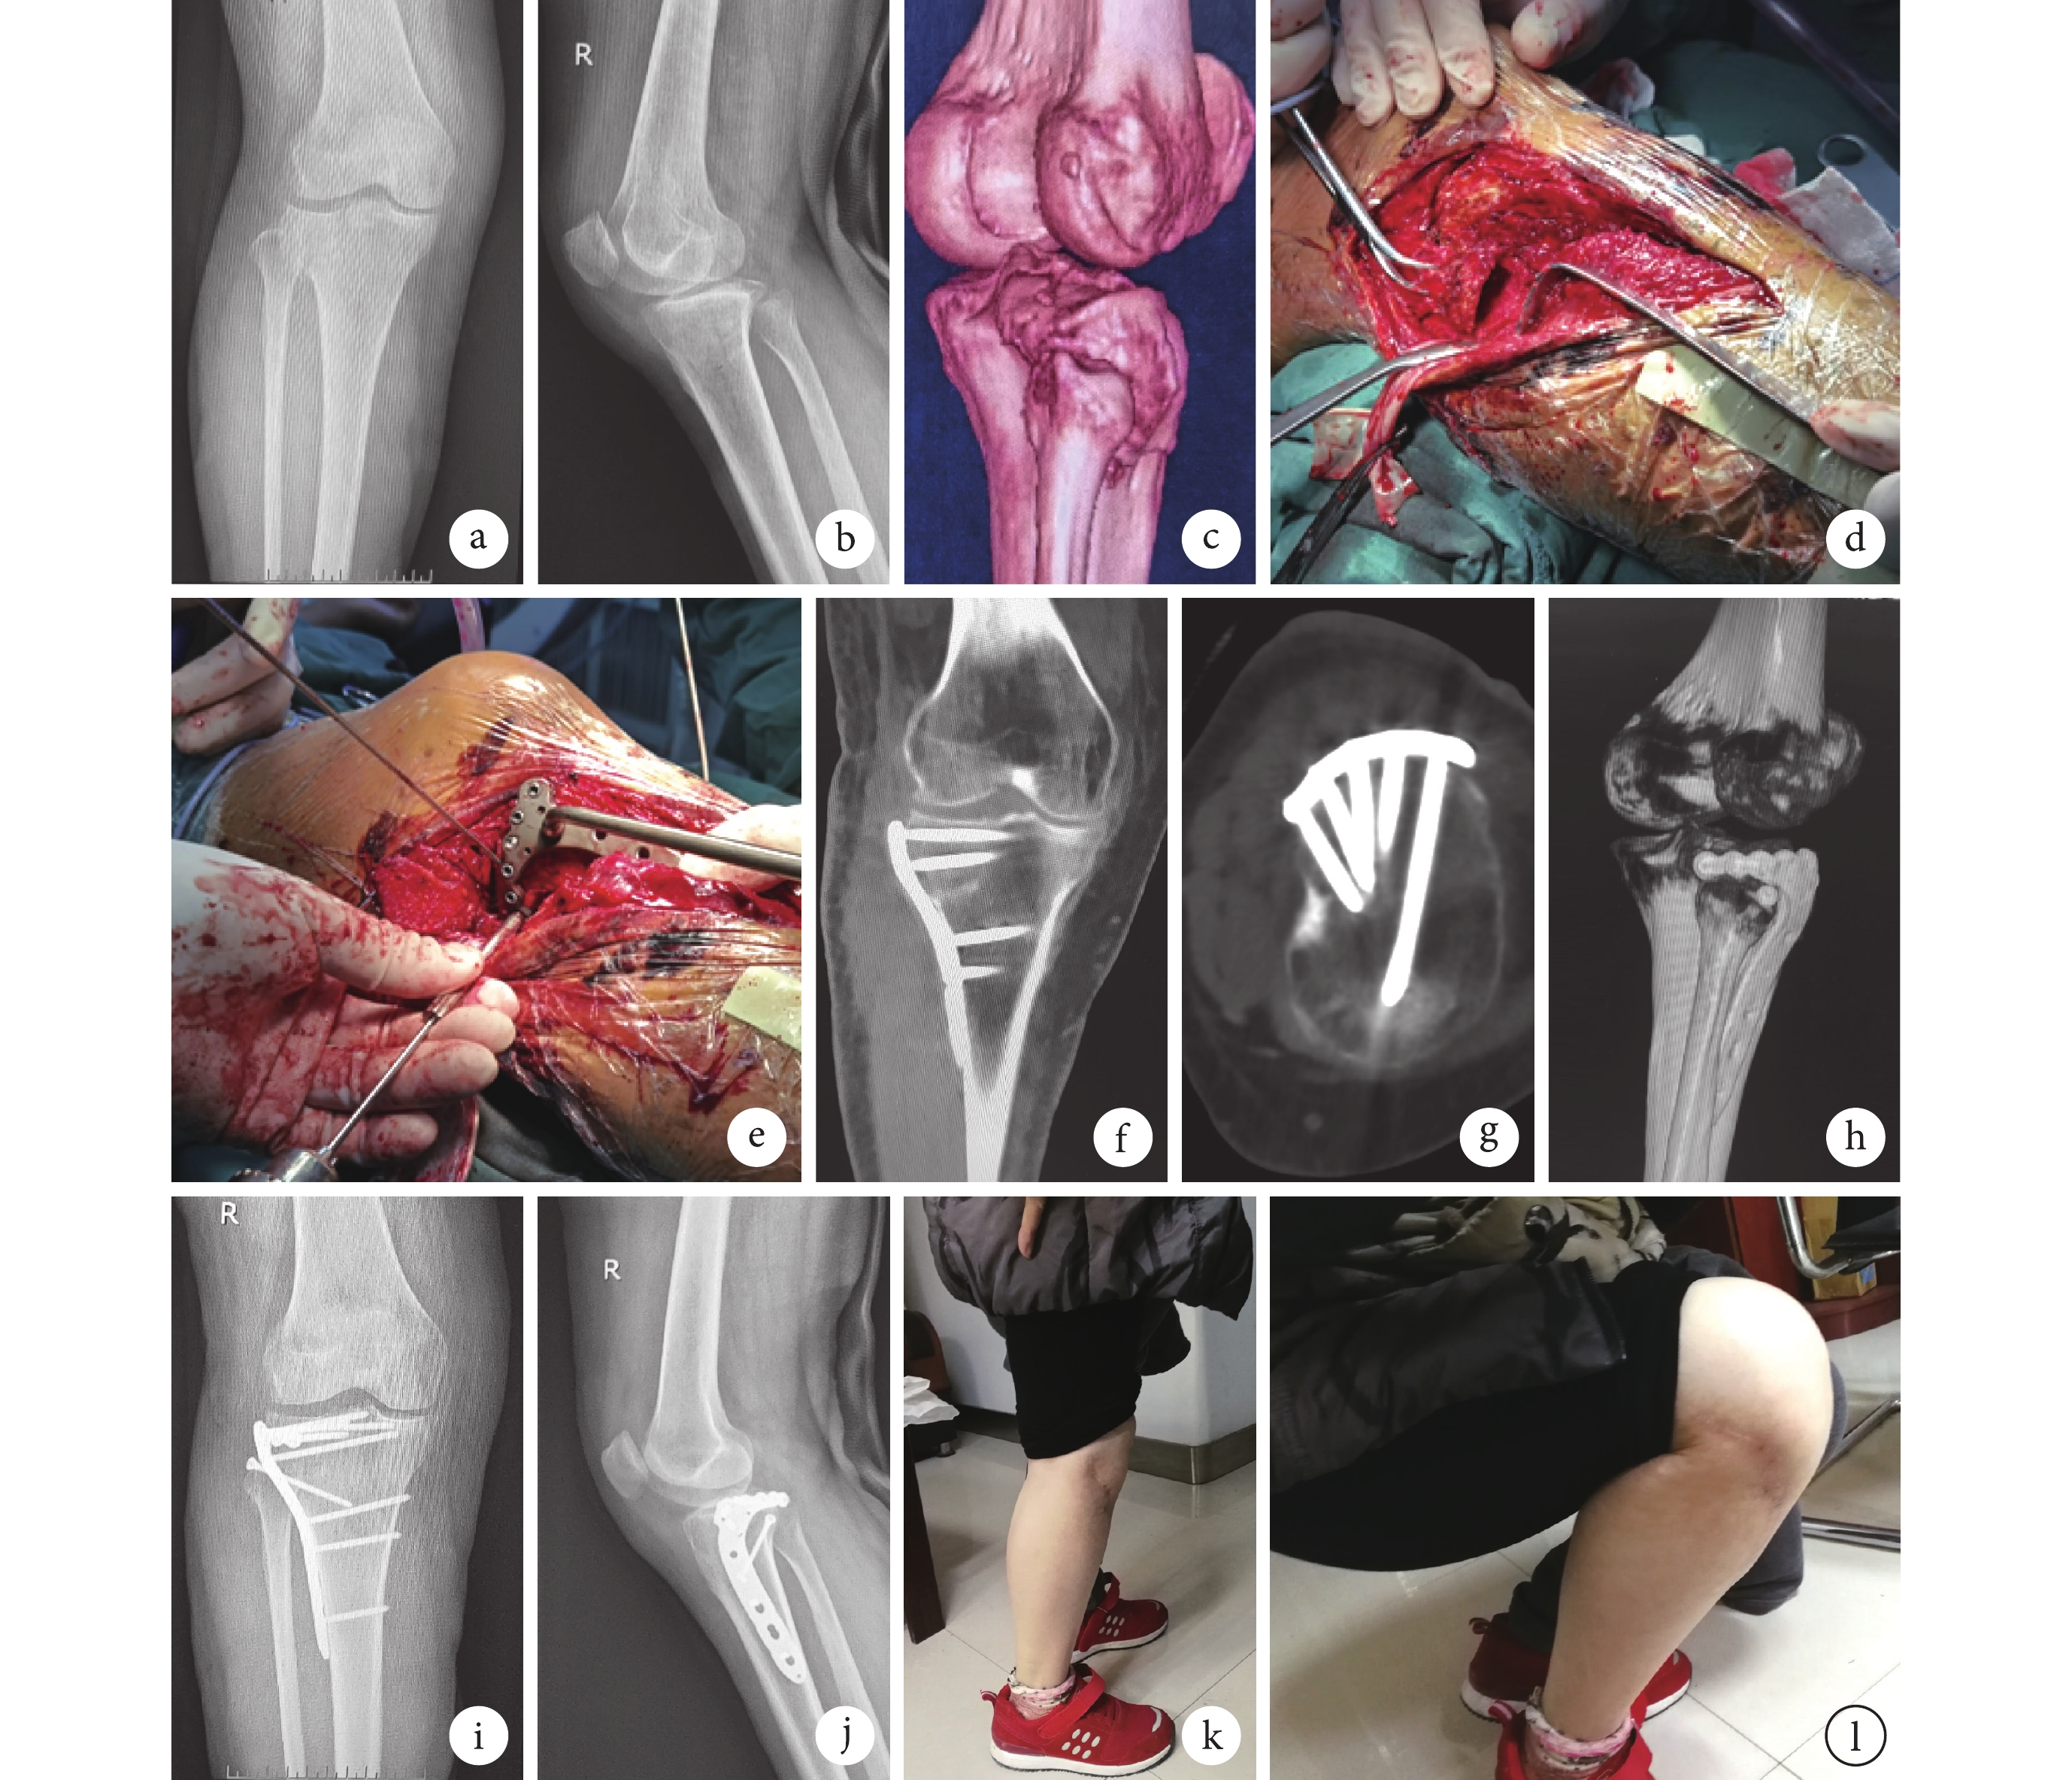

a~c. 術前正側位X線片及CT三維重建;d、e. 手術入路及術中植入新型接骨板;f~h. 術后1周CT掃描及三維重建示骨折復位質量達優,內固定物位置良好;i、j. 術后6個月正側位X線片示骨折愈合良好;k、l. 術后9個月膝關節屈伸功能

Figure2. A 53-year-old female patient with the right posterolateral tibial plateau fracture (Schatzker typeⅡ)a-c. Anteroposterior and lateral X-ray films and three-dimensional CT before operation; d, e. Surgical approach and implantation of the novel plate during operation; f-h. CT scanning and three-dimensional images at 1 week after operation showed good fracture reduction and good position of internal fixator; i, j. Anteroposterior and lateral X-ray films at 6 months after operation showed that the fracture healed; k, l. The flexion and extension functions of knee joint at 9 months after operation

所有手術均順利完成。手術時間60~95 min,平均77.6 min;術中出血量100~520 mL,平均214.5 mL。術后第1天發現腓總神經損傷1例,考慮為術中牽拉以及螺釘植入過程中騷擾神經導致,給予營養神經、脫水消腫等處理,2個月后恢復;術后切口脂肪液化2例,經清創再縫合后切口愈合。22例患者均獲隨訪,隨訪時間13~32個月,平均19.4個月。X線片復查示骨折復位質量達優17例、良5例;骨折均達骨性愈合,愈合時間10~18周,平均13.0周。末次隨訪時,患膝關節活動度達屈曲100°~145°,平均125.5°;伸直0°~4°,平均1.2°。改良HSS評分82~95分,平均86.3分。隨訪期間無鋼板變形、螺釘斷裂、骨折復位丟失、皮膚壞死等并發癥發生。見圖2。